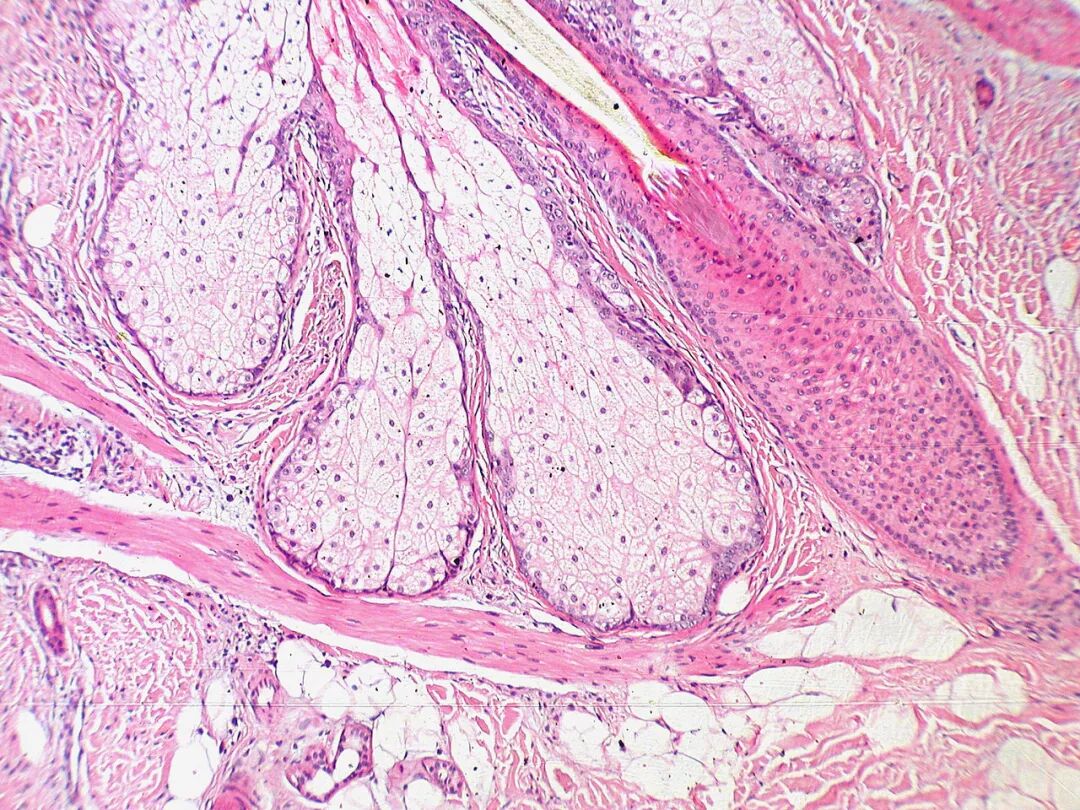

还是没印象?看看这张苏木精-伊红染色的切片,不知道会不会稍微唤起一点你的回忆。图片:Kilbad / wiki commons

为了观察细胞内部的结构,需要用一些东西选择性地染细胞中一部分物质的颜色。苏木精氧化后可以形成苏木因(Haematein),后者可以与某些特定金属离子(主要是三价的铁离子与铝离子)结合形成有色复合物,铝-苏木因复合物呈碱性,可以将核酸染成紫蓝色;而另外一种色素——伊红呈酸性,可以将细胞浆染成粉红色。二者配合使用,便是传说中的苏木精-伊红染色(常缩写为H&E染色),可以清楚地把细胞内的各个组分区分开来,为生物学与医学的发展贡献良多。

经H&E染色的布伦内罗氏瘤切片。图片:Nephron / wiki commons